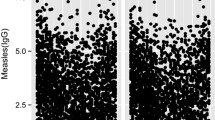

Eighty percent of the study subjects were Caucasians (n = 598, 80.3%), 11.9% (n = 89) were African-Americans, with 44% (n = 328) female, and a median age at enrollment of 15 (IQR 13; 17) years. The median age at the first and second immunization were 15 (IQR 15; 16) months and 5 (IQR 4; 11) years, respectively, and the median time between last measles immunization and sample draw was 7.5 (IQR 5.6; 9.2) years. Median values (25th, 75th percentiles) for MV-neutralizing antibodies in the subjects were 846 mIU/ml (IQR 418; 1,772). Median values for MV-specific IFN-γ Elispot counts for spot-forming cells (SFC per 2 × 105 cells) were 36 (IQR 12; 69). Further, median values for MV-specific IL-2, IL-6, IL-10, IFN-α, IFN-γ, IFNλ-1 and TNF-α cytokine secretions were 38 (IQR 21; 64) pg/ml, 355 (IQR 248; 461) pg/ml, 18 (IQR 11; 28) pg/ml, 551 (IQR 273; 1,025) pg/ml, 67 (IQR 35; 120) pg/ml, 34 (IQR 14; 74) pg/ml, and 14 (IQR 9; 19) pg/ml, respectively.

Genotyping data were analyzed for the combined cohort of subjects (n = 745) and separately for Caucasians (n = 598). We also performed a secondary analysis of data collected for the African-American subgroup (n = 89). Overall, 16 SNPs were significantly associated (p < 0.01) with variations in MV-induced neutralizing antibodies. Six of these SNPs were positioned in the coding and regulatory regions of the TLR2, TLR4, MAP3K7 (TAK1), and TRAF6 genes (Table 1). In the combined cohort of subjects major allele variants AA of two coding synonymous SNPs (rs5030710 and rs3804100) of the TLR4 and TLR2 genes were associated with an allele dose-related decrease (2,209 vs. 830 mIU/ml, p = 0.001) and an allele dose-related increase (660 vs. 892 mIU/ml, p = 0.002) in measles-specific antibody response, respectively. We found significant associations between two promoter SNPs (rs711264, 970 vs. 613 mIU/ml, p = 0.001 and rs806287, 919 vs. 612 mIU/ml, p = 0.005; r 2 = 0.99) located in the MAP3K7 gene on chromosome 6q16.1 and dose-related decreases in measles antibodies. As expected, in the Caucasian and African-American subgroups we found associations for the promoter and coding SNPs in the MAP3K7 and TLR4 genes (rs711264 and rs5030710), respectively. Specifically, increased carriage of minor allele A for rs711264 located in the promoter region of the MAP3K7 gene, was associated with a dose-related decrease in antibodies (974 vs. 612 mIU/ml, p = 0.006) in the Caucasian subgroup. Major allele variant A for a coding SNP (rs5030710; 624 vs. 1,729 mIU/ml, p = 0.009) in the TLR4 gene was associated with an allele dose-related increase in antibodies in the African-American subgroup.

Overall, we found seven SNPs located in coding and regulatory regions significantly associated (p < 0.01) with variations in MV-specific IFN-γ Elispot responses (Table 3). Three significant associations were found with polymorphisms in the KIAA1542 (IRF7) gene region, TLR7 and IKBKE genes and measles-specific IFN-γ Elispot responses in the combined cohort. Specifically, minor allele G for a promoter SNP (rs702966) of the KIAA1542 gene was associated with a dose-related decrease in IFN-γ Elispot responses (38 vs. 26 SFC per 2 × 105 PBMC, p = 0.00002). Analysis in the Caucasian subgroup revealed two significant associations between promoter SNPs (rs2760501, p = 0.001 and rs2984915, p = 0.004; r 2 = 0.93) belonging to the JUN (AP-1) gene on chromosome 1p32-p31 and an allele dose-related decrease in IFN-γ Elispot response to MV. In our secondary analysis of the African-American subjects, we identified two potential associations between promoter SNPs belonging to the MAP3K7 (TAK1) and NFKB1 (NFkB) genes (rs157693, p = 0.001 and rs7674640, p = 0.006) and IFN-γ Elispot responses after measles vaccination.